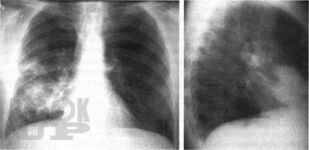

Бронхолегочные синдромы в пропедевтике внутренних болезней

Учебное пособие подготовлено в соответствии с ООП и учебным планом по дисциплине «Пропедевтика внутренних болезней» для обучающихся по специальности 31.05.01 «Лечебное дело». В учебном пособии изложены современные представления об основных синдромах при заболеваниях органов дыхательной системы, необходимых для обучающихся при изучении дисциплины «Пропедевтика внутренних болезней». Учебное пособие оснащено тестовыми заданиями и ситуационными задачами различной степени сложности для самоконтроля знаний с эталонами ответов. Учебное пособие предназначено для самостоятельной внеаудиторной работы обучающихся по специальности «Лечебное дело».